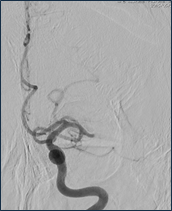

くも膜下出血

脳を包んでいるくも膜という薄い膜と脳の間に動脈が走っています。その動脈の壁に動脈瘤という膨らみが出来て、それが破れて起きるのがくも膜下出血です。この病気を起こす危険因子として高血圧、飲酒、喫煙が挙げられます。突然の激烈な頭痛で発症するのが特徴で、突然後ろから後頭部をバットで殴られたような痛みと表現されることもしばしばです。痛みの程度は出血量と関係しますので少量のくも膜下出血では頭痛の程度はそれほど強いものにはならないこともあります。頭部CTにより診断はつきますが、出血が少ない場合、見逃されることもありますのでぜひ専門医のいる病院をすぐ受診して検査を受けてください。破裂した脳動脈瘤を放置しておくとまず間違いなく再出血します。そのため再破裂、再出血予防の処置が必要となります。しかしながら昏睡状態やきわめて全身状態の悪いときには残念ながら手術治療のできない場合もあります。

くも膜下出血のCT

【くも膜下出血のCT】

Apoplexy 14

【脳動脈瘤;矢印の部位】

治療の方法は、開頭して動脈瘤にクリップをかけるクリッピングという方法と、コイル塞栓術といって頭を開けないでカテーテルで治療する方法があります。どちらの手段にも有利な点と不利な点があり、当院では動脈瘤の場所、形状、患者さんの状態などに応じて両者を使い分けています。